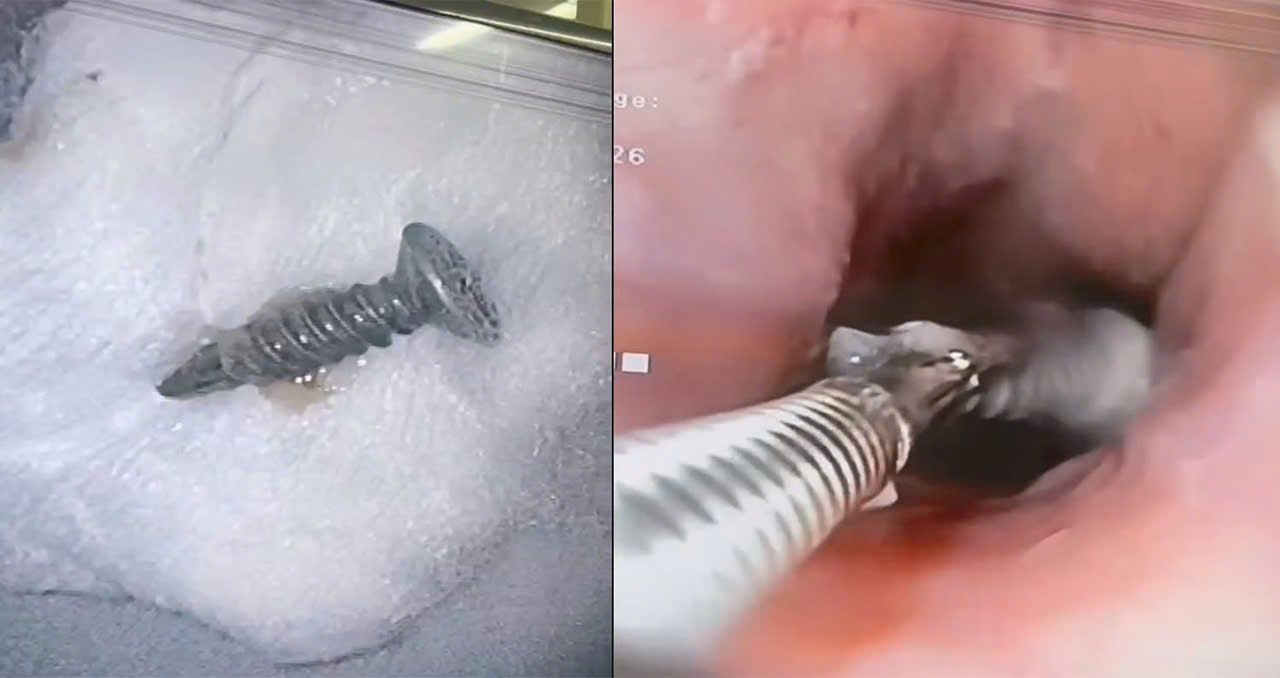

Thách thức của ca bệnh nằm ở chỗ chiếc đinh có đầu sắc nhọn và chiều dài đáng kể, rất dễ đâm thủng thực quản hoặc niêm mạc dạ dày trong quá trình kéo ra ngoài. Bằng sự khéo léo và phối hợp nhịp nhàng, sau hơn 15 phút tập trung cao độ, kíp thủ thuật đã sử dụng dụng cụ chuyên dụng để “bắt” gọn chiếc đinh kim loại dài khoảng 4 cm ra khỏi cơ thể bệnh nhân một cách an toàn, không gây thêm tổn thương cho đường tiêu hóa.

Ngay sau thủ thuật, bệnh nhân đã tỉnh táo, tình trạng đau bụng giảm rõ rệt và được tiếp tục theo dõi tại khoa. Khuyến cáo từ chuyên gia Trao đổi về ca bệnh, Thiếu tá, Ths. BS Lê Thị Thái Bình, Phó chủ nhiệm khoa Nội Tiêu hóa – Máu cho biết: